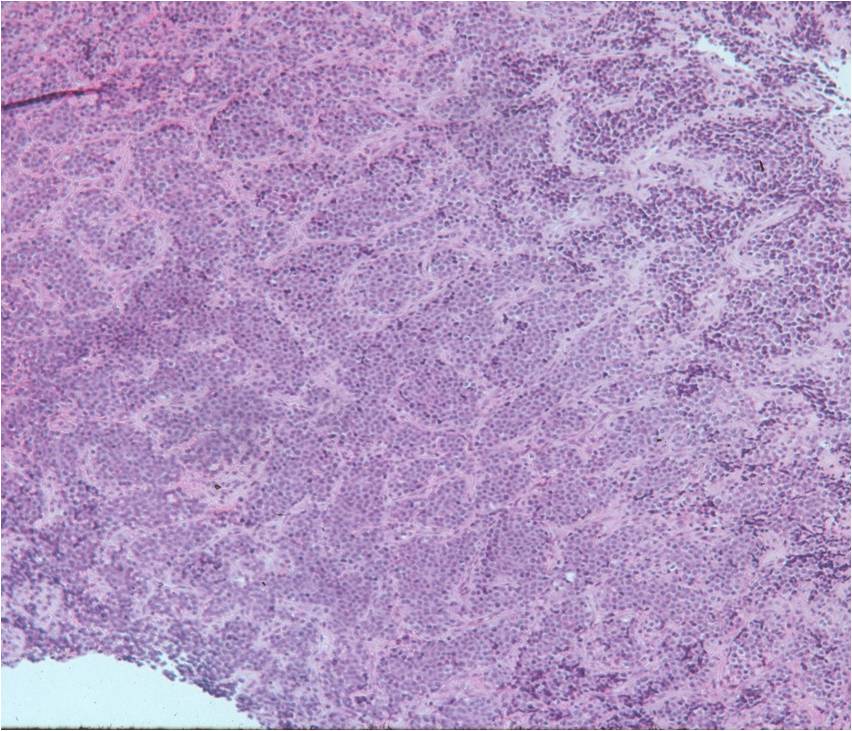

- Ewing sarcoma is composed of undifferentiated, small round, polygonal mesenchymal cells rich in glycogen

- Sheets of uniform cells with scanty pale cytoplasm and indistinct cell boarders

- No Matrix

- Nuclei are round/oval with finely dispersed chromatin

- Cells are similar in appearance

- Geographic necrosis with perivascular sparing

Small Round Blue Cells No Matrix Large Nuclei No Cytoplasm